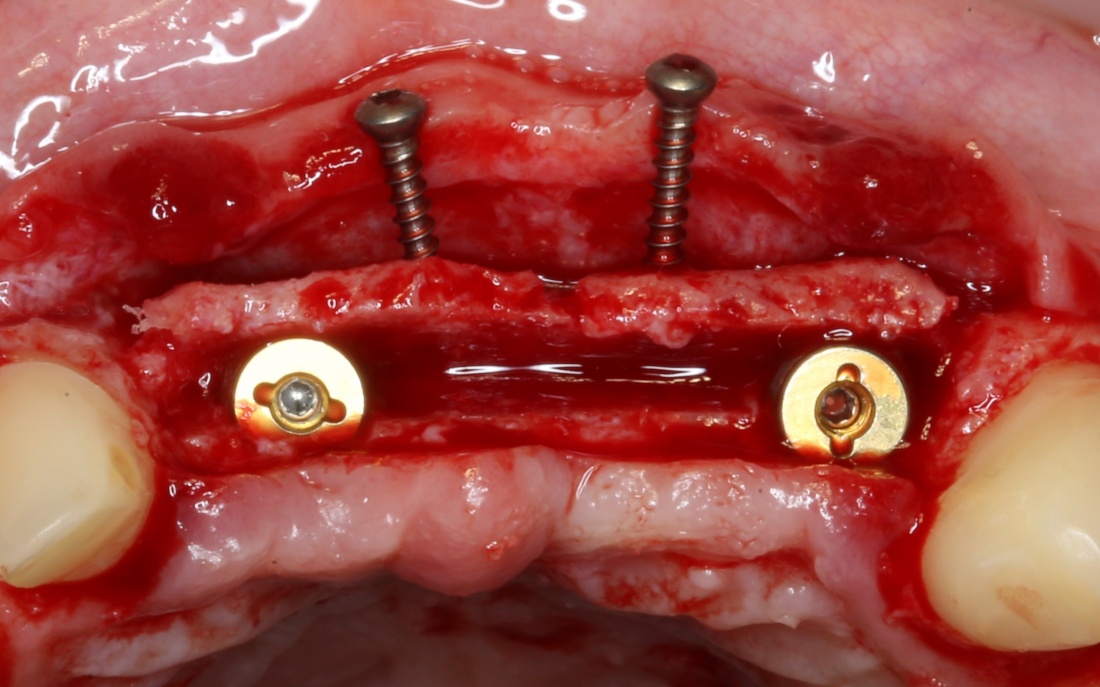

Установка имплантатов

По ряду уже упомянутых выше причин, для решения этой клинической задачи мы выбрали имплантаты Xive. Лунки для них мы уже приготовили. возможную первичную стабильность оценили. Имплантаты мы установили с усилием чуть больше 15-20 Нсм — такого крутящего момента более, чем достаточно, особенно если учесть, что временные коронки будут соединяться между собой.

Подробно о том, что такое крутящий момент и хирургический протокол можно прочитать здесь>> и тут>>, соответственно. Из-за использования специальных индивидуализируемых временных абатментов, имеющих только три положения, нам нужно позиционировать платформу имплантатов по граням. Это очень просто  — мы выводим вырез абатмента TempBase (он входит в комплект поставки) вестибулярно.

После перкуторной проверки стабильности имплантатов и точности позиционирования, мы переходим к следующему этапу — сохранению десневого контура.

Установка имплантатов занимает около двух минут.